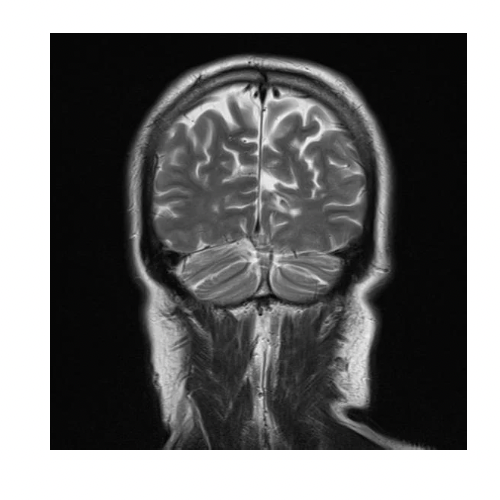

頭部MRI

脳の中の撮影をします。主に脳梗塞、脳腫瘍、脳動脈瘤などの病変がないかを確認します。